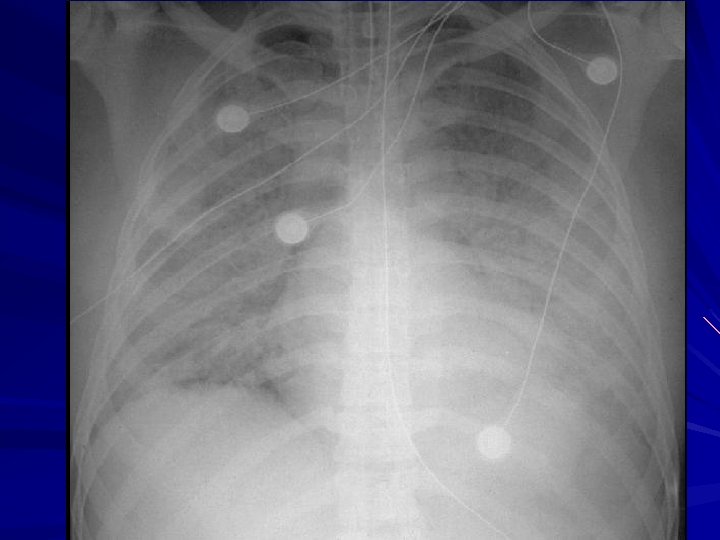

Acute Respiratory Distress Syndrome Causes: - Aspiration Pneumonia - Near Drowning - Chest Trauma - Severe Pneumonia